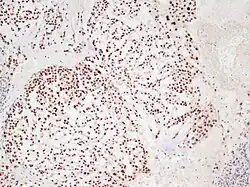

In 2015 the first consensus guidelines for the diagnosis and treatment of chordoma were published in The Lancet Oncology.[13] These tumors express brachyury and cytokeratin, which can be detected by immunohistochemistry.

There are three histological variants of chordoma: conventional,[14] chondroid and dedifferentiated.

- The histological appearance of classical chordoma is of a lobulated tumor composed of groups of cells separated by fibrous septa. The cells have small round nuclei and abundant vacuolated cytoplasm, sometimes described as "physaliferous" because of their cytoplasmic vacuoles, and their resemblance to the physalis plant.

- Chondroid chordomas histologically show features of both chordoma and chondrosarcoma.